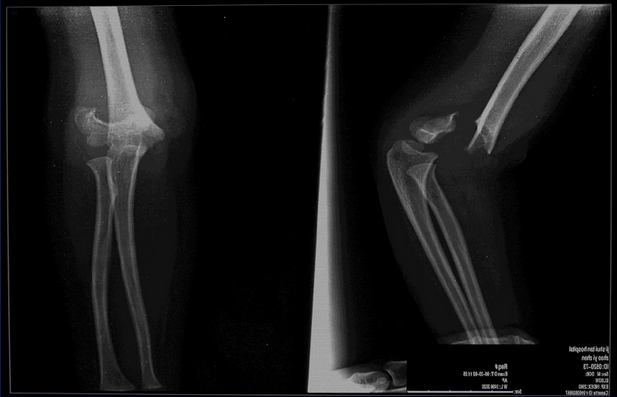

2.伸直尺偏型

外力来自肱骨髁部的前外侧,肱骨髁受暴力作用,使肱骨髁上骨折的远侧端向尺侧和后侧移位。此类骨折的内移和内翻的倾向性大,骨折移位时必须加以整复,以避免肘内翻畸形。

3.伸直桡偏型

外力来自肱骨髁部的前内侧,骨折后,远侧骨折端向桡侧和后侧移位,这种骨折不易发生肘内翻畸形。

2.X线检查:可见骨折线。